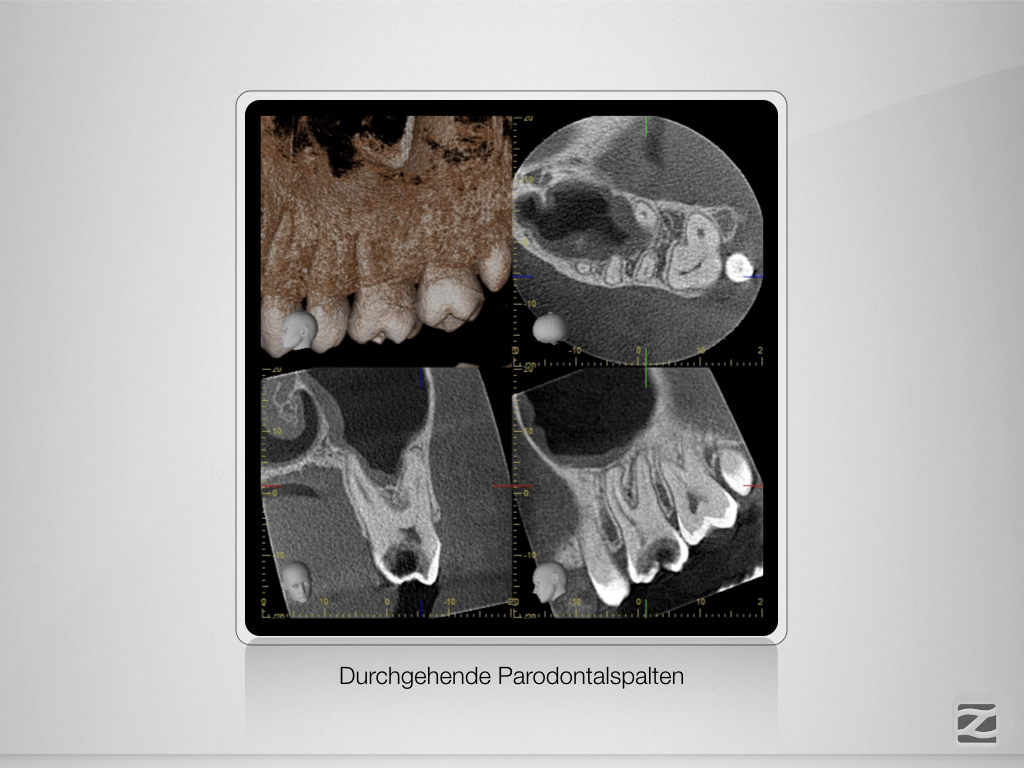

26D.006

Alternativlos?